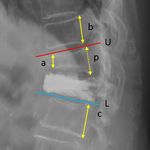

Figure 2.  Measurement of the anterior body height and focal kyphotic angle. a, anterior body height of the

VCF; b, posterior vertebral height of the adjacent cranial vertebra; c, posterior vertebral height of the adjacent

caudal vertebra; p, estimate of the posterior body height of the VCF (average of b and c). The anterior body

height ratio is a/p; U, the line parallel to the upper endplate of the cranial vertebra (red line); L, the line parallel

to the lower endplate of the caudal vertebra (blue line). The focal kyphotic angle is the intersecting angle of U

and L.

ratio of the newly fractured vertebra and the focal kyphotic angle (Fig. 2), and clinical outcomes (based on the

frequency of analgesics prescription in the outpatient clinics) within 2 years. We divided the patients into two